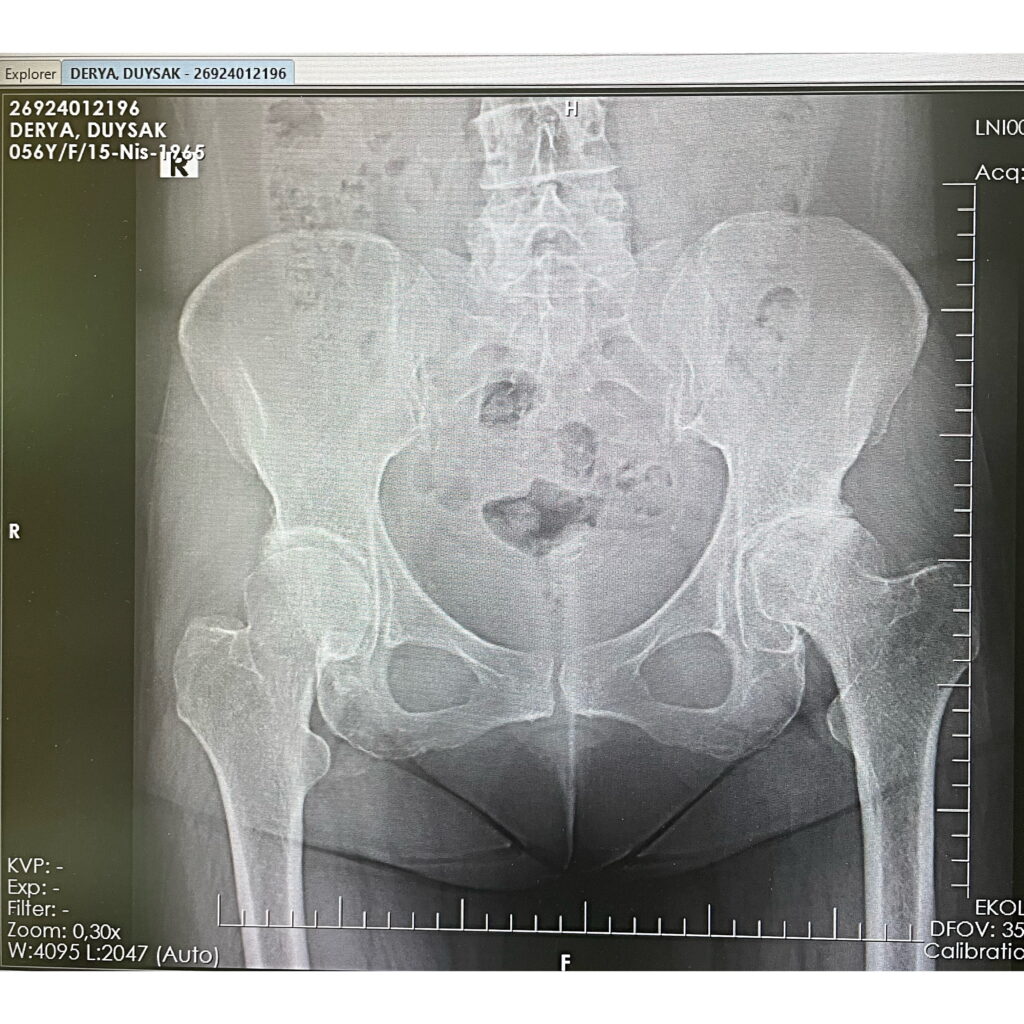

D.D.